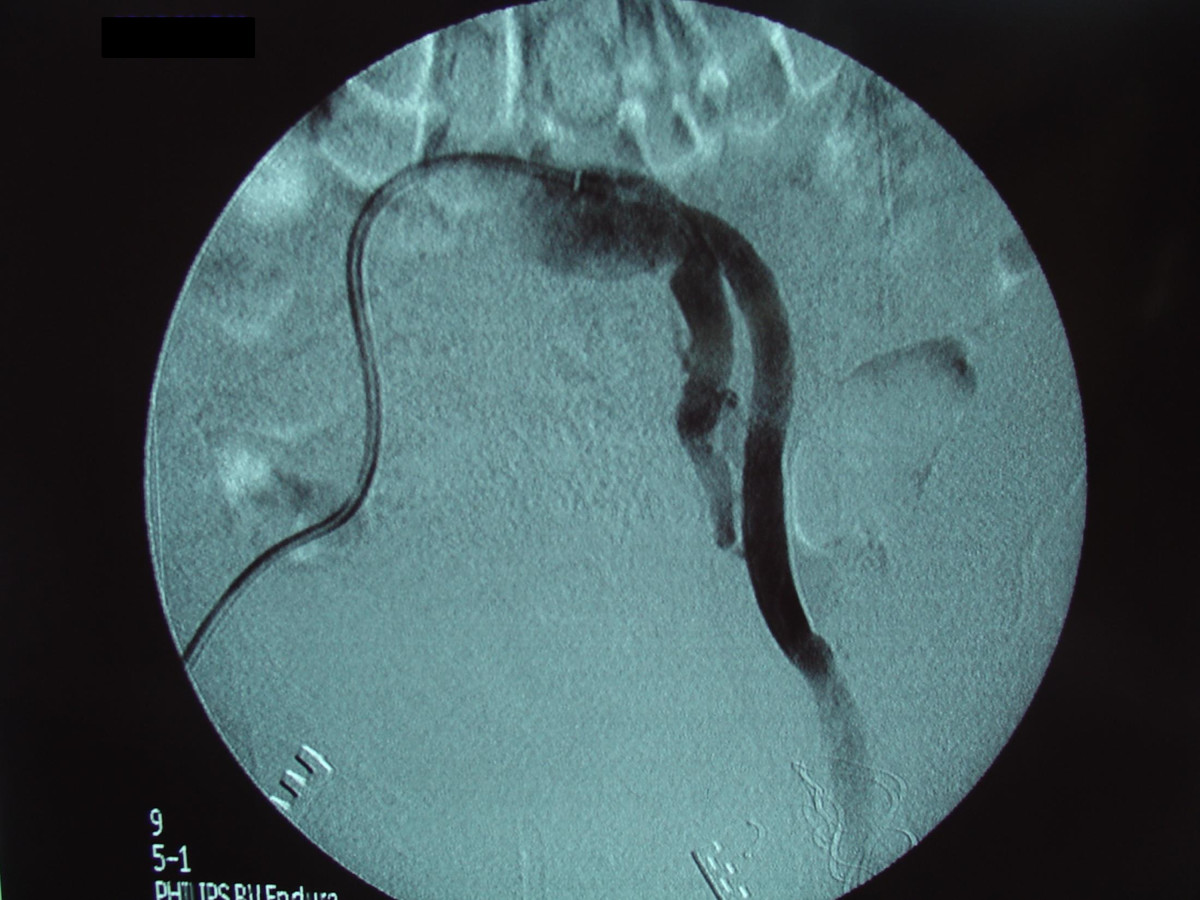

Ενδαγγειακή αποκατάσταση ανευρυσμάτων κοιλιακής αορτής

12ο Πανελλήνιο Συνέδριο Αγγειακής και Ενδαγγειακής Χειρουργικής

2010, Αθήνα